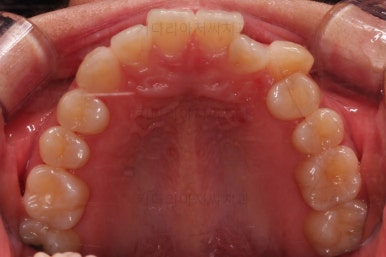

1. 초진

초진 시 입안의 모습입니다.

덧니가 눈에 띄고요.

맞물림이 긴밀하지 못한 상태였습니다.

전반적으로 약간 삐뚤지만 많이 심하다고 보긴 힘들었습니다.

덧니가 있는 방향으로 치열들이 쏠리고 틀어져 중앙선이 맞지 않는 양상이었습니다.